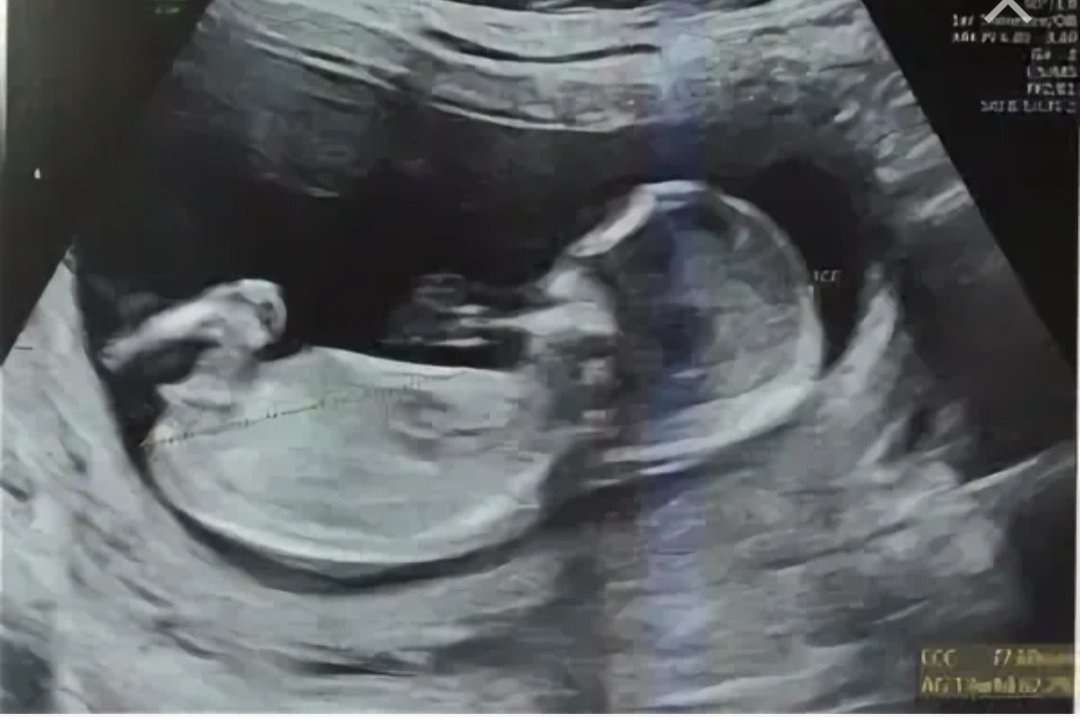

Мы провели УЗИ органов малого таза, в процессе которого увидели в полости матки плод, соответствующий сроку 16 недель. Также был выполнен анализ крови на ХГЧ (45 000 мМЕ/мл).

В данный момент пациентка находится на 35 неделе беременности и ждет мальчика.